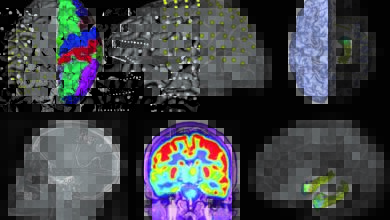

Early Warning of Seizures Can Be Groundbreaking for Epilepsy Patients

Epilepsy is one of the most common neurological conditions, affecting more than 65 million worldwide. For those dealing with epilepsy,…